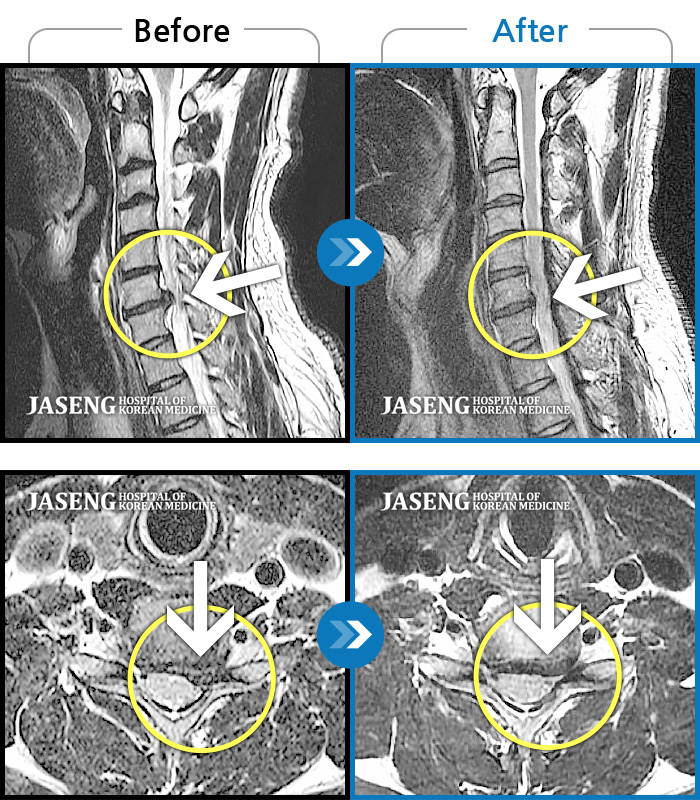

자생 비수술 한방통합치료 후

터진디스크가 흡수된 모습

비수술 치료만으로

터진 디스크 흡수

Before

After

양측 승모근 통증과 목 통증, 견갑골 통증으로 고개를 돌릴때 통증을 호소하는 환자였습니다.

2019.11.18 ~ 2024.07.30